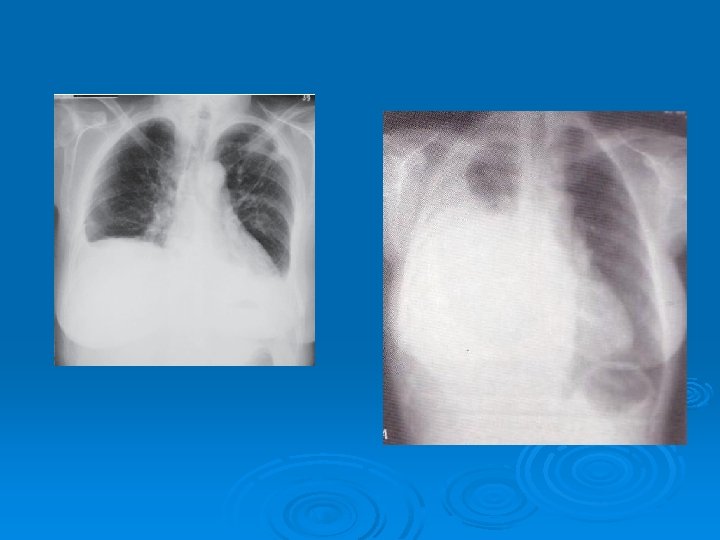

Ø The most common clinical presentations are dyspnea, chest pain, unilateral decreased volume of the affected hemithorax (frozen chest) (inspite of fluid accumilation) Ø Nodular thickening of the pleura, irregular thickening of the interlobar fissure, absence of mediastinal shift with massive pleural effusion (frozen chest) Diagnosis by histologic examination Ø Treatment oncologic and surgical if possible, prognosis is poor Ø